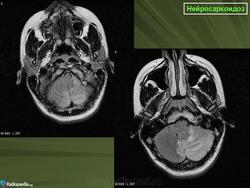

ID: 17921 Neurosarcoidosis Dr Frank Gaillard - 25 May 2012 The case demonstrates typical features of neurosarcoidosis, which are of...

Случай 1: с участием лептоменинга

Случай 2: с участием паренхимы

Случай 3

Случай 4: вокруг гипофизарного стебля

Случай 5: вовлечение спинного мозга

Случай 6: вовлечение гипофизарного стебля

Рисунок 8

Рисунок 8 Нейросаркоидоз.